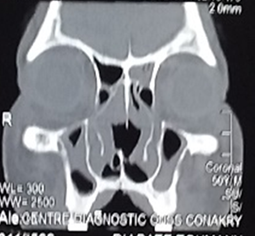

The CT scan of the facial mass showed bone and cartilage lysis, irregular thickening of the nasal pyramid, continuity of the nasal septum, and isodensity of the maxillary, ethmoidal and left sphenoidal sinus walls without total filling (Figures 3&4). The chest radiograph was normal.

Figure 3 The CT scan of the facial mass showed bone and cartilage lysis, irregular thickening of the nasal pyramid, continuity of the nasal septum.

Figure 4 The CT scan of isodensity of the maxillary, ethmoidal and left sphenoidal sinus walls without total filling.